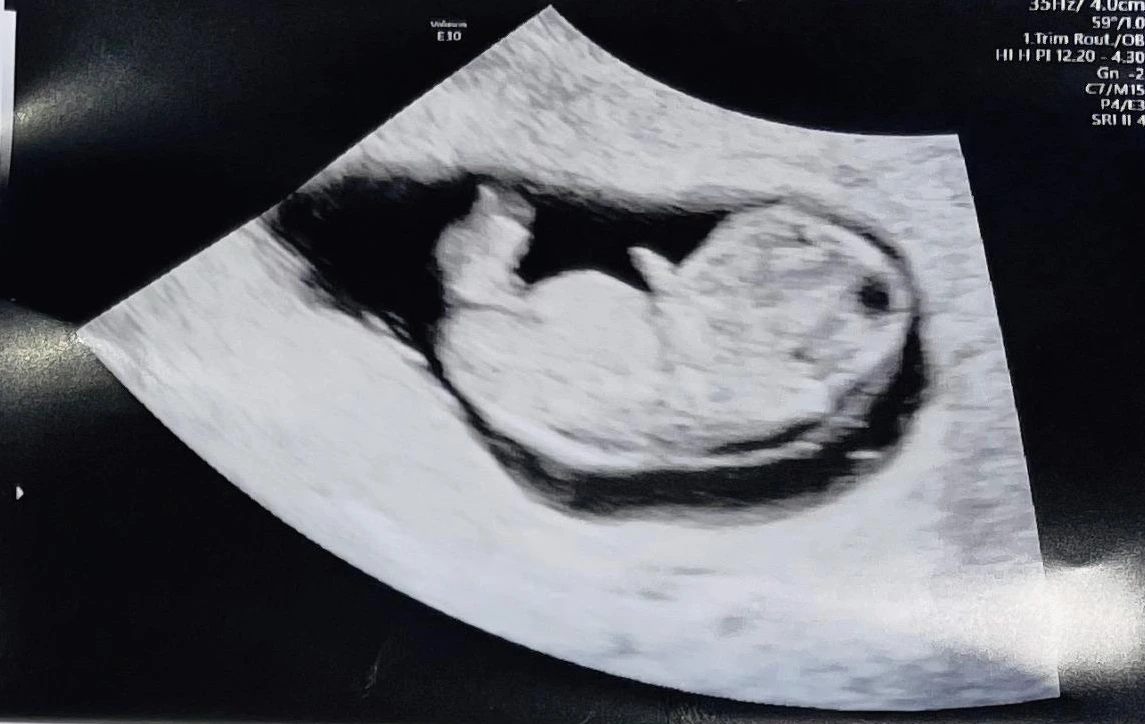

9주 경, 출혈 양상이 달라져 병원으로 달려갔다. 나는 불안했지만 괜찮다는 듯 잘 놀고 있던 아가. 설마 나중에 초상권 운운하며 엄마를 원망하지는 않겠지요.